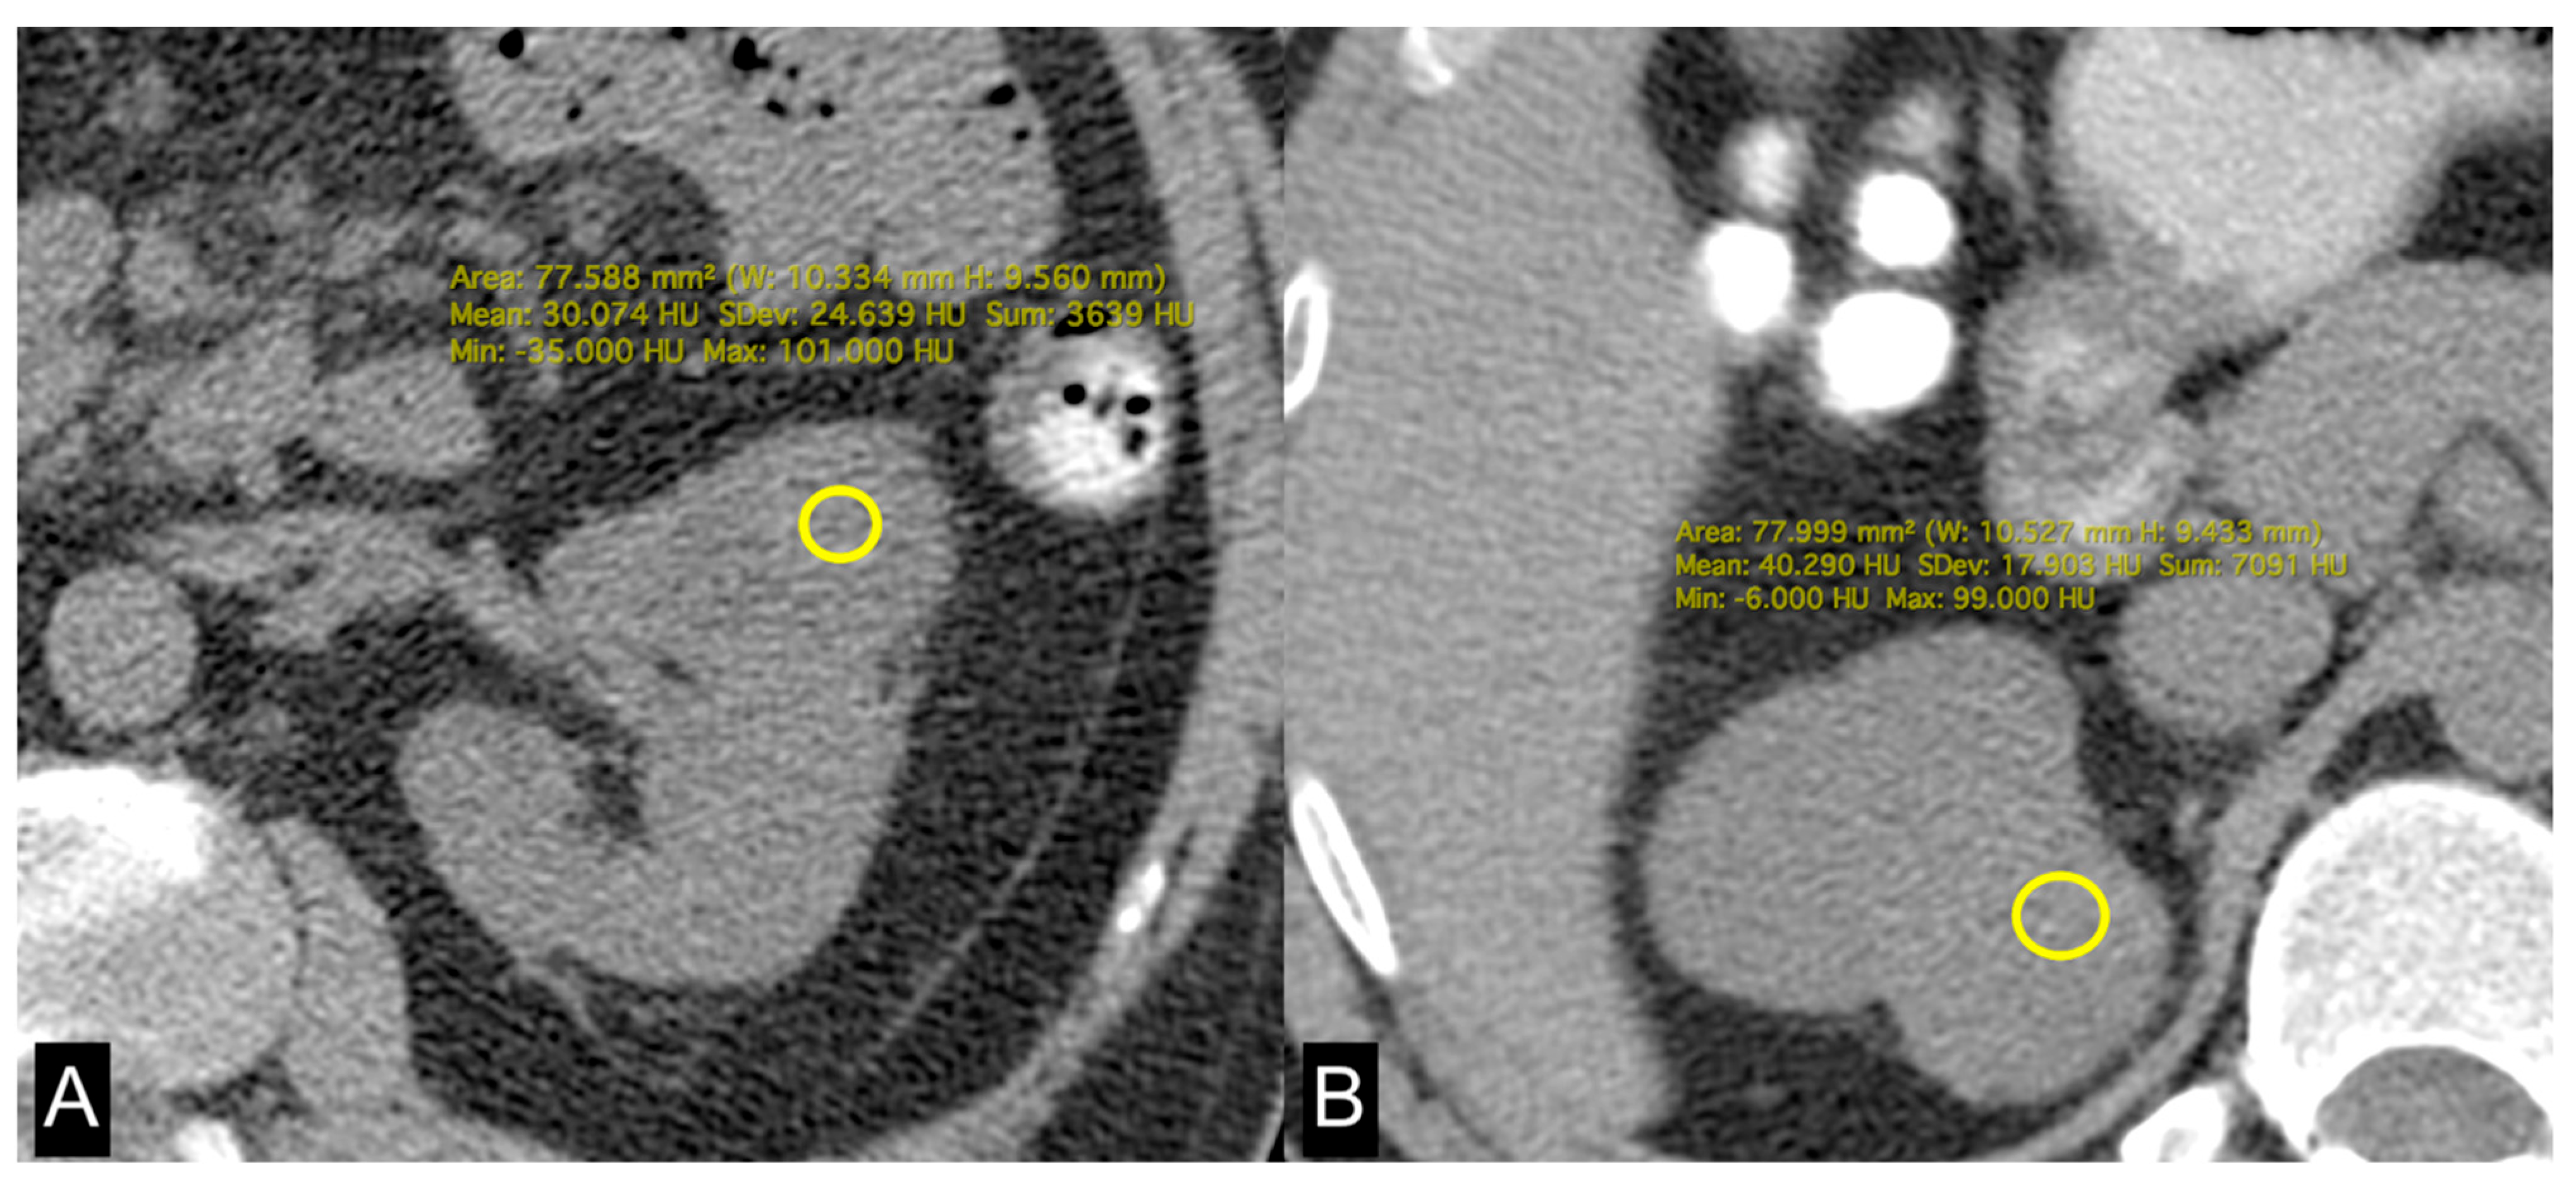

2.3. Lipid Metabolism Imaging Features

| HU | 34 (27, 37) | 36 (32, 42) | 0.021 |

| HU | 30 (24, 32) | 37 (33, 40) | 0.002 |